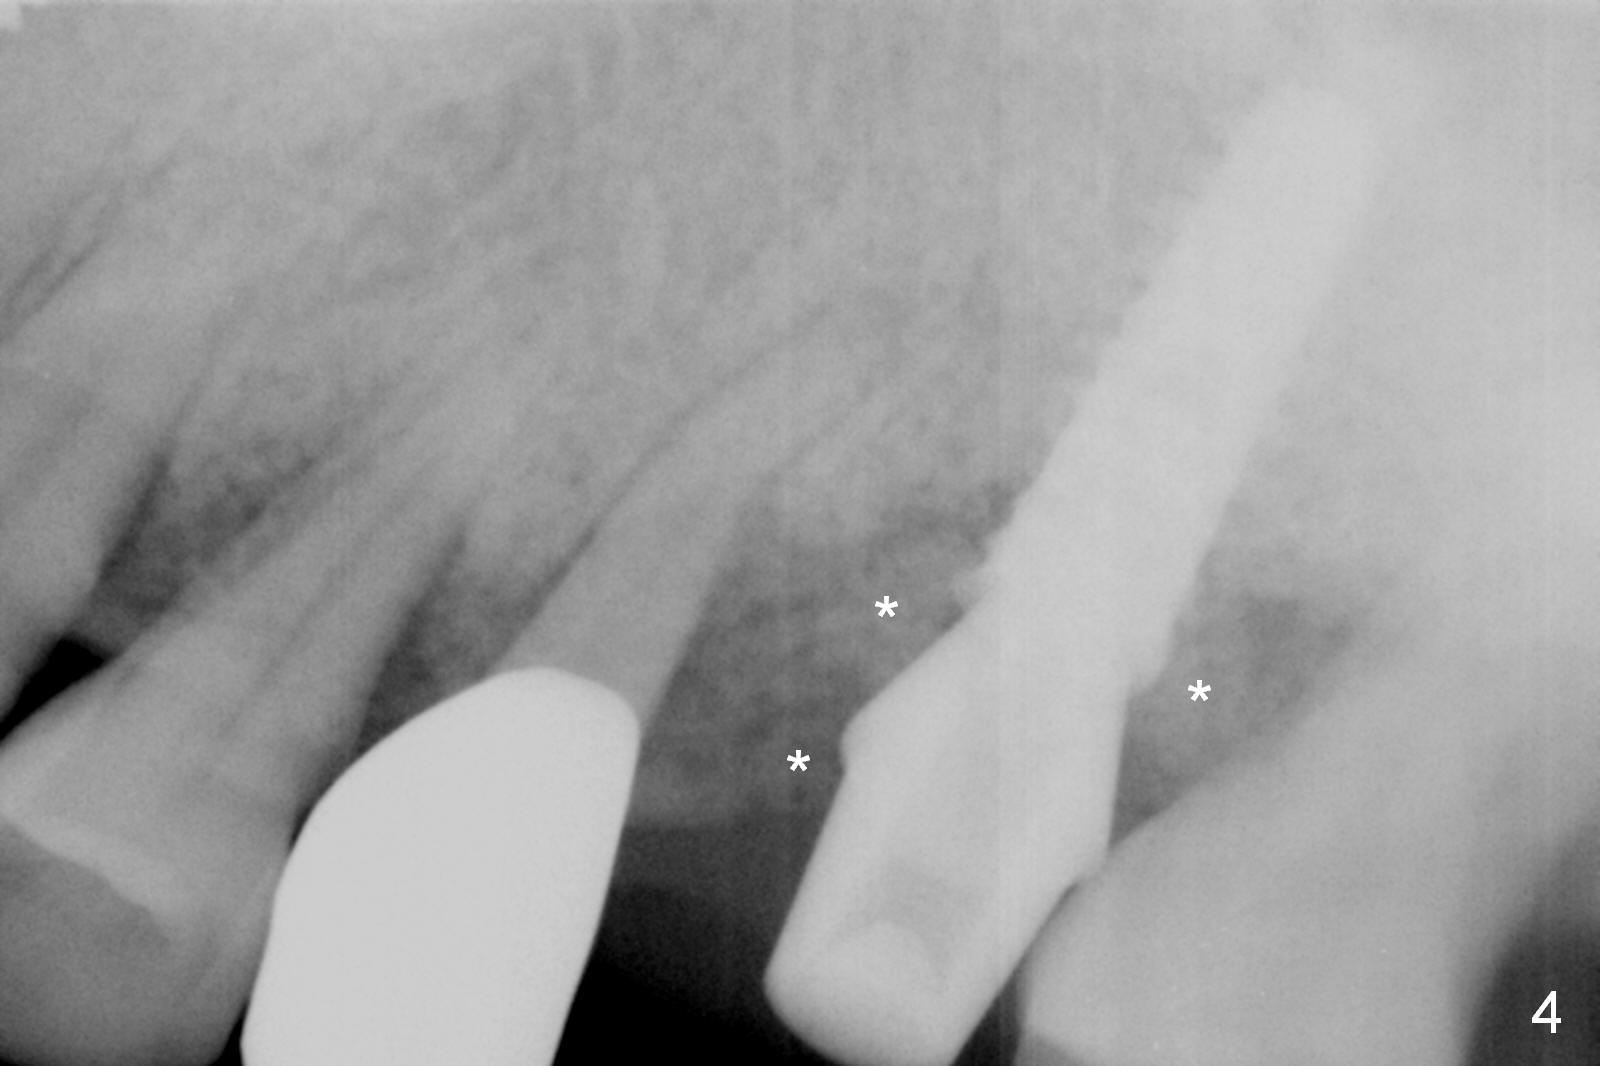

Preop exam show that the tooth #14 appears to be more severe than #18. When the former is extracted with forceps (not so easy), the mesial portion of the mesiobuccal root splits. The latter may be the reason for discomfort and one of the outcomes of advanced peridontitis. The septum is wide enough to use 4.3 mm Magic Drill (MD) following 1.6 mm pilot drill and Marking bur. A 5x13 mm IBS implant is placed apical to the mesial and distal crest and coronal to the septum (Fig.2,3). Insertion torque is ~ 35 Ncm. A 6.0x5.7(4) mm pair abutment is chosen over a 6.5 mm one, because the implant is placed somewhat distally (Fig.4,5). If the implant were placed more apically, the 4 mm cuff would be short for restoration. Allograft and autogenous bone harvested from the MD is placed around the coronal portion of the implant and the abutment cuff (*). Acrylic is spread around the abutment to hold the bone graft in place (without trimming).

The amount of the bone graft mesial and distal the implant seems to reduce 3 and 4 months postop, respectively (Fig.6,7 arrowheads). When the acrylic is cut off 4 months postop, the bone graft is loose. The gingiva is unhealthy. The abutment and implant are loose. A healing abutment is placed (5x4 mm). The implant is torqued to 35 Ncm 6 months postop with the healing abutment reapplied. The patient will return for follow up nearly 9 months postop. A larger healing abutment will be used if the implant is stable. Two weeks later, use a smaller restorative abutment for easy impression. In fact the implant is unstable with #15 mesial shift due to abnormal occlusion with #17 (Fig.8). Bone density around the implant is low (* in Fig.9 (PA), 10,11 (CT sagittal, coronal sections)). A healing screw is placed for self healing. A 2nd option is to remove the implant (Fig.12), BEB (Fig.13) and place the implant deeper (Fig.14) or larger one (5.5-6.5x13 mm). The 3rd option is to place larger and longer implants (Fig.15 (tapered), 16 (cylindrical)). The implant access has partially closed 14 months postop, but there is a small buccal opening with sanguine exudate. Incision reveals severe bone loss around the implant; the mobile tooth #15 is extracted (Fig.17). After debridement and irrigation with normal saline, Vera Graft (Fig.18 *) and Collagen plug are placed with periodontal dressing.